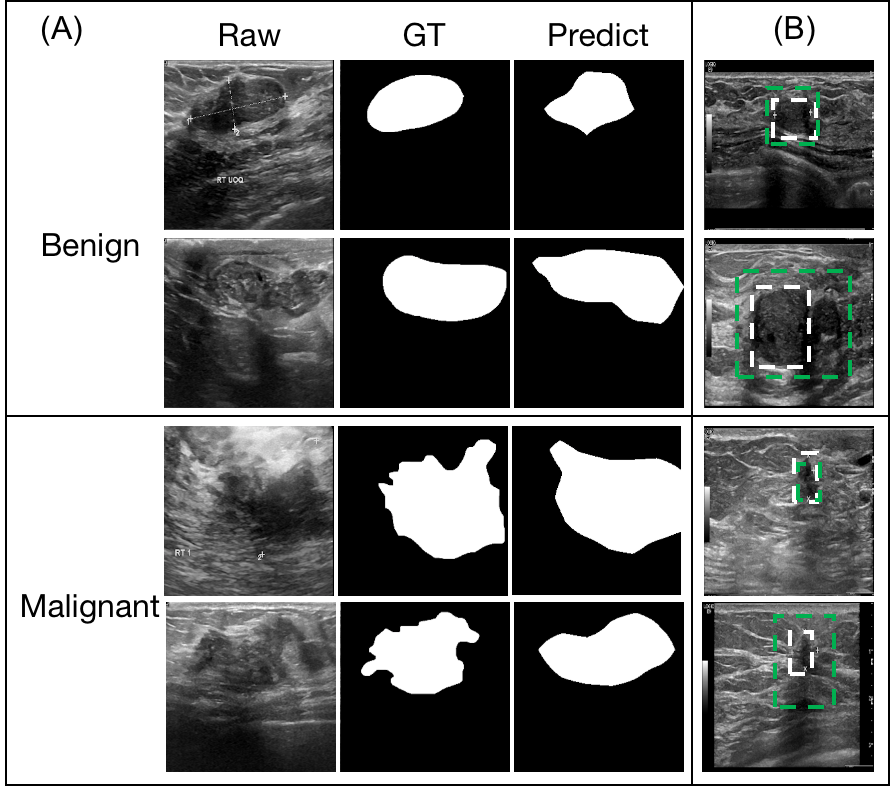

4.2 Localization performance of the proposed method

Several BUS examples and their predicted lesion masks are shown in Figure 7 for qualitative analysis of the localization performance of our method. The lesion masks were achieved by up-sampling the output of the LA-Net to the size of the input image and then binarized with a threshold of . These predicted lesion locations generally show impressive overlap with their GT lesion locations, especially on the BUD dataset annotated with accurate segmentation contours. The predicted lesion locations are less precise when using F-MBUD dataset, probably due to the location annotation in the form of bounding boxes.